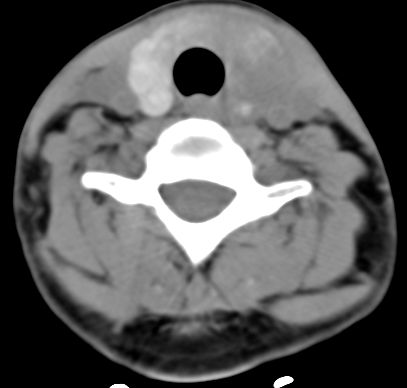

标题: CT9717:F、30Y、颈部左侧包块半年,压痛.患者拒绝作增强。 [打印本页]

标题: CT9717:F、30Y、颈部左侧包块半年,压痛.患者拒绝作增强。

病人不做强化就不太好说了,但结合病人年轻女性,有压痛,还是考虑良性病变,以桥本氏病可能性大。可结合化验结果综合考虑。

结合病史:考虑亚急性甲状腺炎可能性大。(不知道病人有没有检测tsh t3 t4)

多为亚急性甲状腺炎症。最好结合检验结果进一步检查。

考虑桥本氏甲状腺炎,

支持;甲状腺炎症性病变.----亚急性甲状腺炎可能大.

2,亚急性甲状腺炎.临床多见,发病年龄较轻,由上呼吸道感染或病毒性腮腺炎后发病.临床触痛明显.然局部皮肤无红热.t3t4早期升高,后期降低.病灶可单侧或双侧.易炎性渗出,使脂肪密度增高.

3,桥本甲炎(慢性淋巴细胞性甲炎);自身免疫有关.t3t4降低.中老年女性多见.甲状腺弥漫增大,基本对称.,峡部最明显.边界较清.

桥本氏